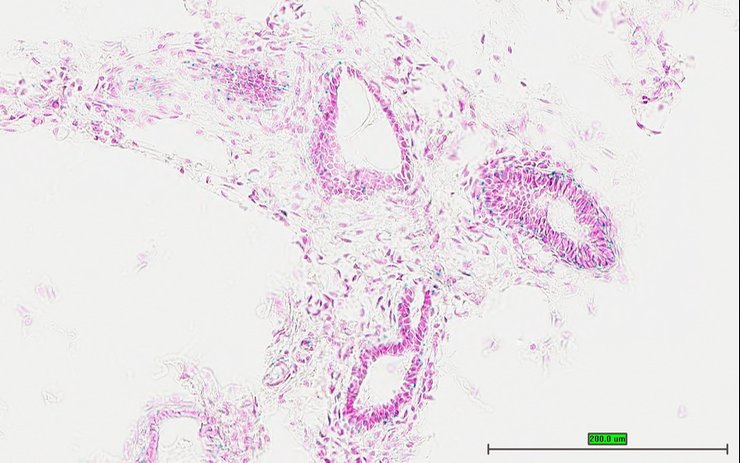

TS28: lung Present UC Davis_1879521

Specimen UC Davis_1879522: postnatal adult; Dlg5tm1b(EUCOMM)Wtsi/Dlg5+ (more )

Structure Level Pattern Image Note

TS28: thymus Present UC Davis_1879522